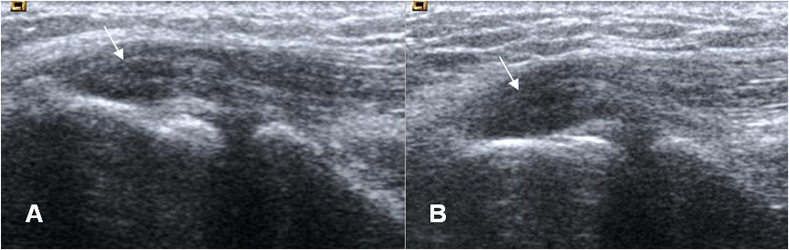

Fig 49 D. Epicondilitis lateral.

A: Ecografía sagital. Apariencia normal en el origen común de los tendones extensores.

B: Ecografía sagital. Origen de tendones engrosado e hipoecoico, por cambios inflamatorios. (Flecha gruesa). Muestra áreas ecogénicas por fibrosis secundaria a tendinitis crónica o ruptura parcial. (Flecha delgada).